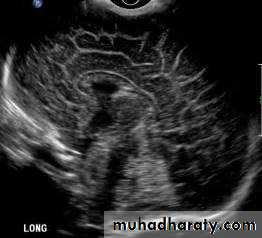

• Transvaginal US (TVUS): accurate assessment of gynecological problems and of early pregnancy up to about 12 weeks’ gestation

• Endoscopic US (EUS): assessment of tumors of the upper gastrointestinal tract and pancreas